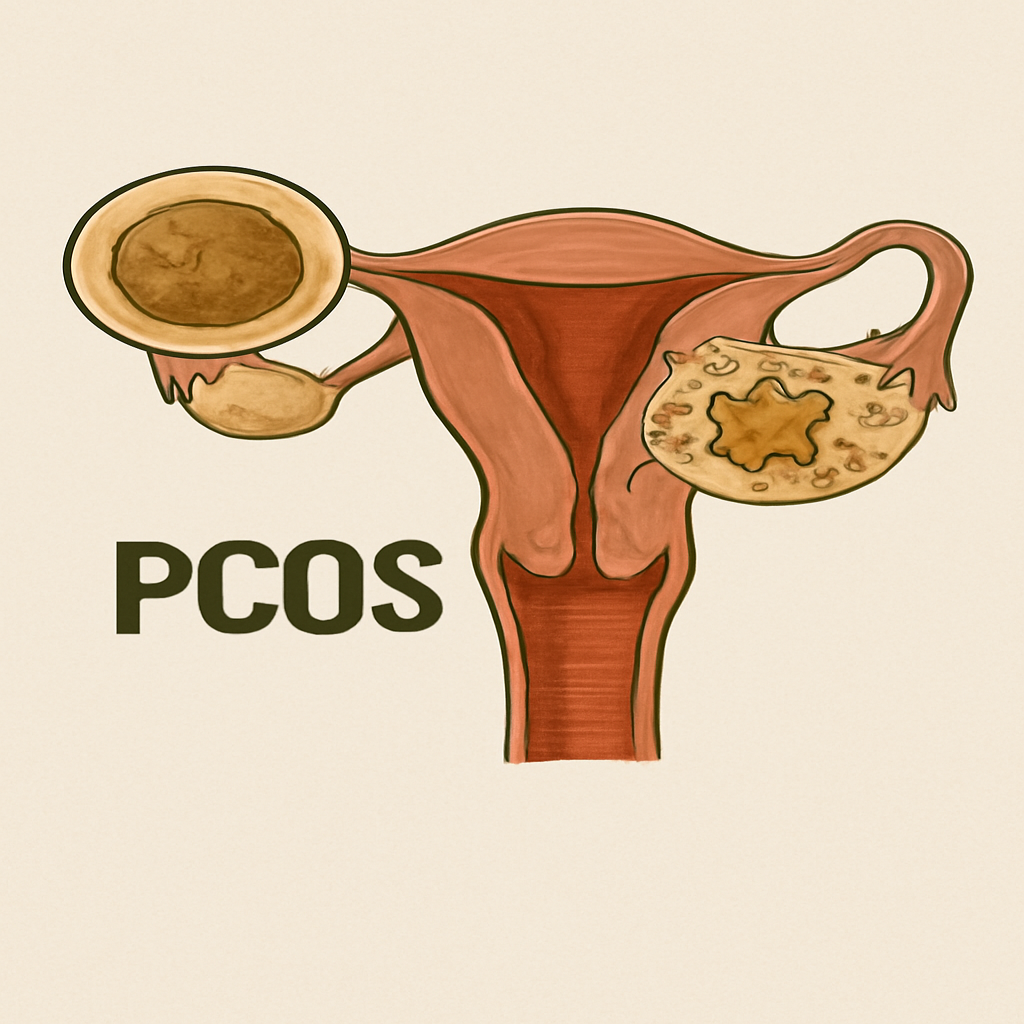

# Female